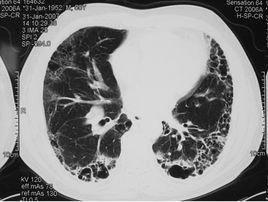

普通型间质性肺炎

双肺下叶间质性纤维化属于间质性肺炎(interstitial pneumonia)病变反应,系细菌、支原体或病毒所致。多见于